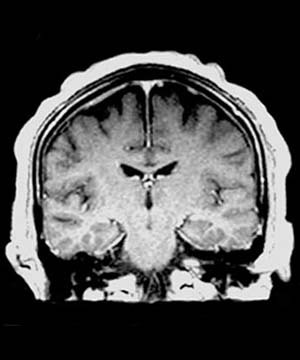

Because of its low sensitivity and specificity for the diagnosis of Alzheimer's disease, imaging is typically not used to rule in Alzheimer's disease but rather to rule out other causes of dementia. Nevertheless, in the right clinical context Alzheimer's disease appears radiographically as diffuse cerebral atrophy with enlarged lateral ventricles and widened sulci on CT. On thin-section (3 mm thick) coronal T1-weighted MR, medial temporal lobe atrophy primarily in the amygdala, hippocampus, and parahippocampal gyrus may be visually evident. Utilizing MR volumetric measurements, the hippocampal formation may be quantitatively determined to show focal atrophy. In addition, the temporal horns, supracellar cisterns, and Sylvian fissures may exhibit focal symmetric or asymmetric enlargement.

![]() ![]() MR has been chosen for the above images because of its ability to show greater detail in Alzheimer's disease. |